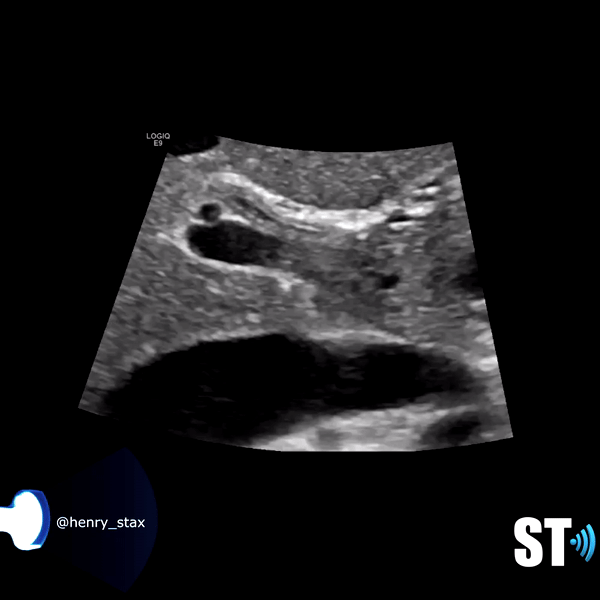

Patients may be asymptomatic (up to 50%) or may have symptoms of biliary colic in the ruq or epigastrium. Other symptoms like pruritus, pale stools and intermittent jaundice may be present. On sonography will see biliary dilatation, depending on the location and size of the stones there may be GB enlargement and intrahepatic biliary dilatation as well. There will be echogenic stones with posterior acoustic shadowing. There may be one stone or multiple. At times the ductal stone may be distal to be observed with US, as such an Endoscopic Retrograde Cholangiopancreatography (ERCP) or Magnetic Resonance Cholangiopancreatography (MRCP) may be necessary for diagnosis.

Distal

Sonographically the most common findings in patients with cholangiocarcinoma is biliary dilatation. Papillary tumors resemble polypoid intraluminal masses. Nodular cholangiocarcinoma manifests as a discrete smooth mass associated with wall thickening. Infiltrating cholangiocarcinoma is the most common type but is difficult to evaluate with sonography.